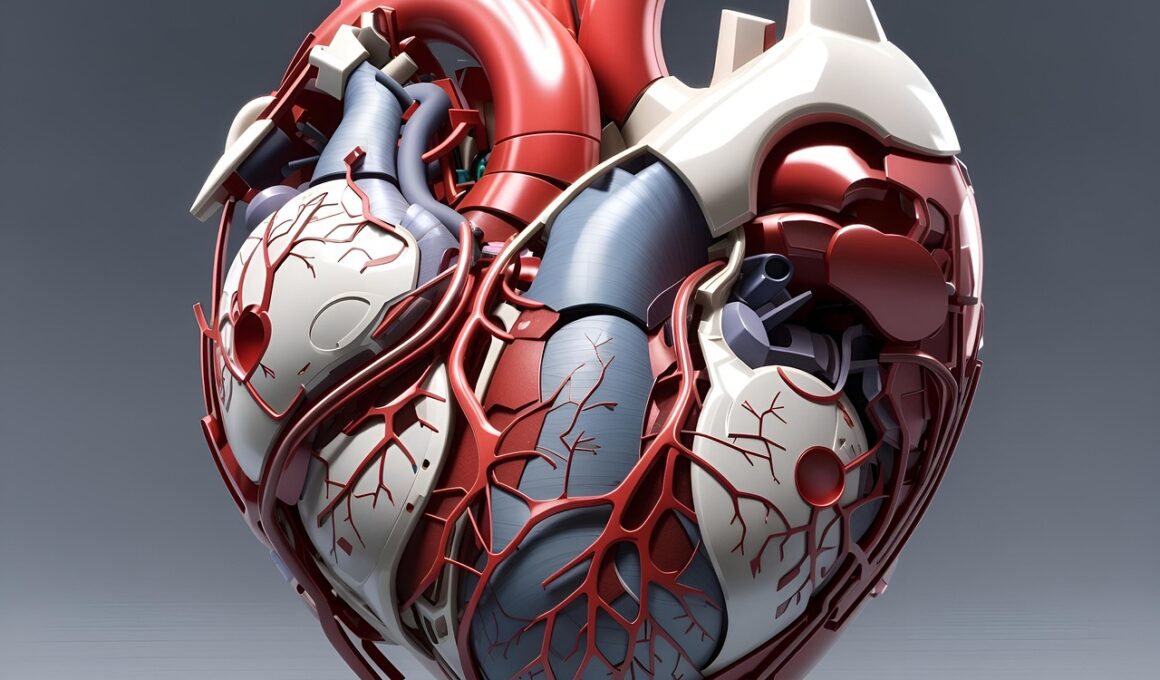

Competitive athletes often overlook cardiovascular risks, focusing intensely on performance. However, cardiovascular health plays a crucial role in overall athletic ability and longevity. Factors such as family history, training intensity, diet, and lifestyle choices can influence the heart’s condition. Athletes frequently endure rigorous training schedules that, while enhancing performance, may increase the risk of undiagnosed heart issues. This concern emphasizes the importance of regular cardiovascular assessments. Screening tests can facilitate early detection of potential problems. Recognizing the warning signs of heart distress, such as chest pain or unusual fatigue, is essential. Additionally, incorporating heart health into training routines can enhance performance and safeguard against potential medical emergencies. Athletes should not only be aware of their cardiovascular status but also proactively manage it. Engaging with medical professionals for tailored advice can produce significant benefits. Cardiovascular endurance, strength, and flexibility should be prioritized in conditioning programs. Comprehensive health plans focusing on cardiovascular training can foster lasting resilience. Remember that a healthy heart supports peak athletic performance while ensuring long-term benefits beyond the sports arena. Regular check-ups, proper hydration, and balanced nutrition contribute significantly to maintaining optimal cardiovascular health.

Regular heart assessments are vital for athletes striving for excellence. Cardiovascular diseases can strike even the fittest individuals, making it imperative to monitor heart health consistently. Testing reveals hidden risks that common training regimens cannot address. Medical professionals may recommend heart stress tests or echocardiograms to gauge fitness levels safely. Such evaluations provide insights into cardiovascular performance under stress. Athletes should consult sports cardiologists who understand the unique aspects of high-intensity sports. This specialized focus helps detect issues early, ensuring athletes remain in peak condition. Ensuring your heart is healthy before major competitions prevents potential crises. Consequently, including heart-focused exercises in training regimens aids in building endurance. Proper warm-up routines maintain heart health during strenuous activities. Athletes must learn to identify their body’s signals; ignoring warning signs might lead to severe consequences. This knowledge enables informed discussions with healthcare providers regarding individual risks. Moreover, athletes should stay educated on nutrition, hydration, and lifestyle choices that impact cardiovascular performance. Remember, an athlete’s achievements are intertwined with heart health, requiring ongoing commitments to monitoring. By prioritizing regular assessments, athletes ensure their best performance while minimizing health risks throughout their careers.

Genetic predispositions play a pivotal role in cardiovascular health. Family history of heart disease raises awareness and informs athletes about their risks. Some athletes may carry genetic markers linked to certain heart conditions. As such, staying proactive concerning heart health is crucial. Genetic testing, when advised by healthcare providers, can yield insights into personal risks. This information arms athletes with knowledge, allowing them to adjust their training or lifestyle accordingly. Understanding one’s genetic framework aids in making informed decisions. Health professionals can provide preventive strategies tailored to specific genetic backgrounds. Additionally, athletes must balance environmental factors, like training location and lifestyle habits with their genetic predispositions. Maintaining a dialogue with healthcare teams about family medical history is vital. Athletes should inquire about assessments or screenings that might be beneficial. Ultimately, the combination of genetics and lifestyle plays an essential role in determining cardiovascular outcomes. Awareness and education foster resilience by preparing athletes to address risks. Adopting heart health as a priority in training contributes positively to longevity and performance. Learning about personal genetic influences empowers athletes to take their health and careers into their hands.